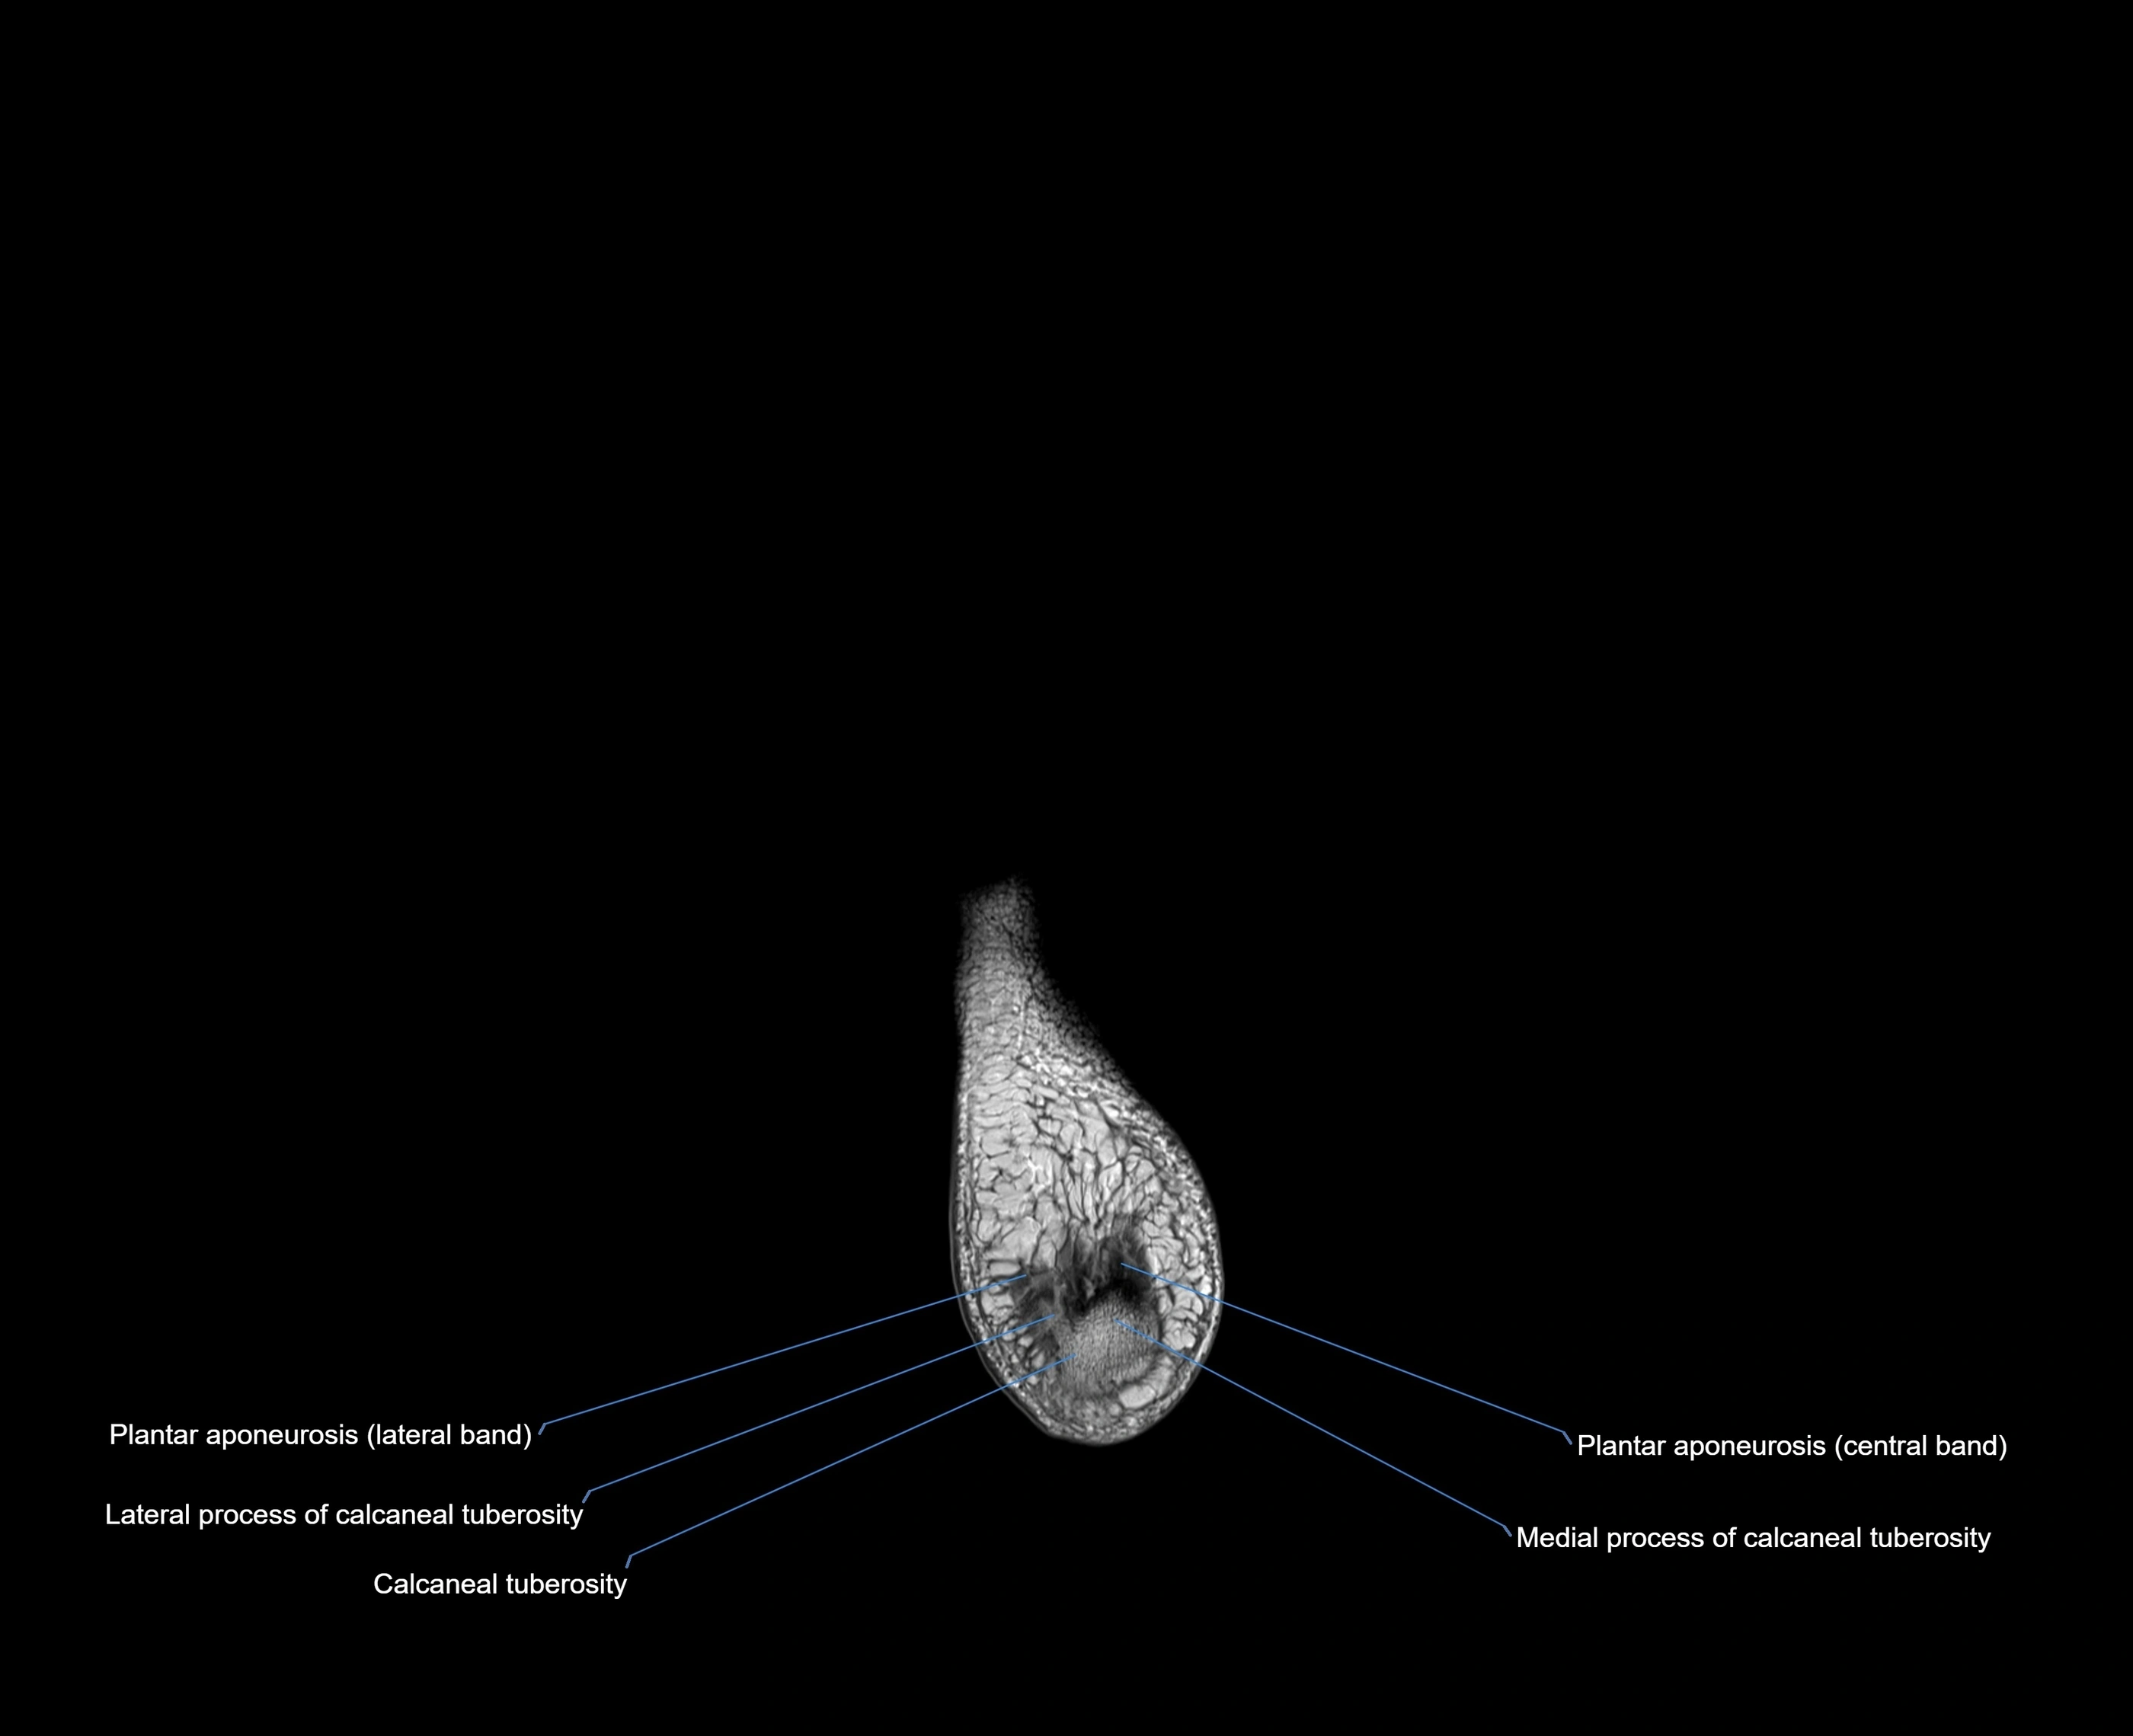

- Calcaneal tuberosity

- Lateral process of calcaneal tuberosity

- Medial process of calcaneal tuberosity

- Plantar aponeurosis